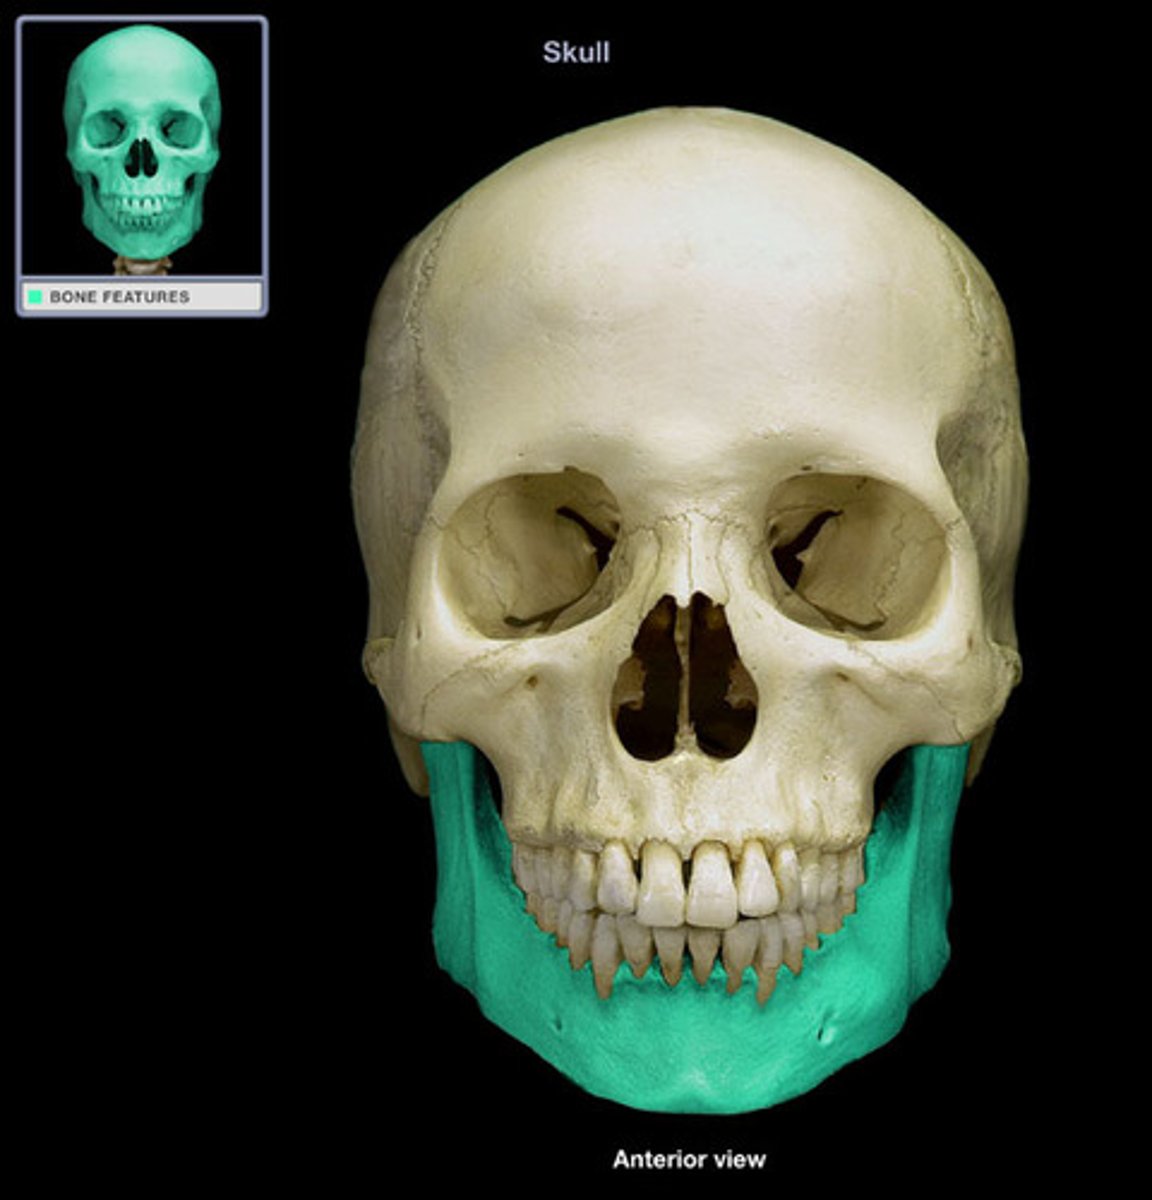

mandible

body of mandible

rami of mandible

gonion

mental protuberance (mentum)

symphysis of mandible

Aveolar Process of Mandible

mental foramina

coronoid process of mandible

condylar process

mandibular notch